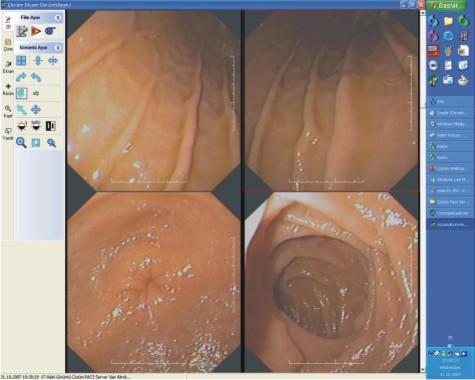

PACS (Picture Archiving And Communication System): sayısal olarak elde edilen panoramik ve lokal radyolojik görüntülerin (ultrasonografi (USG), doppler, magnetik rezonans (MR), tomografi (BT) v.b. cihazlardan elde edilen verilerin) çevrimiçi ortamlarda sayısal arşivleme yöntemleriyle saklanması, gerekli yer ve zamanda hızla yeniden istemcide görüntülenip değerlendirilmesine olanak sağlayan Radyoloji Bilgi Sistemi (RIS) ile birlikte çalışan sistemden oluşuyor. DICOM (Digital Imaging and Communications in Medicine):  Sayısal görüntülerin iletilmesi, saklanması ve yazdırılması için oluşturulmuş bir standartlar topluluğundan oluşuyor.

Çözüm PACS ile sayısal görüntüler arşivlenebiliyor, yönetilebiliyor ve değerlendirme yapılabiliyor.

Çözüm PACS'da, Manyetik Rezonans, Bilgisayarlı Tomografi, Anjiyografi ve Ultrasonografi, Mammografi vb cihazlardan üretilen sayısal görüntüler depolama mimarilerini (SAN, NAS, DAS vb) destekleyen merkezi veri tabanında, sunucuda saklanıyor.

Arşiv sunucusu üzerindeki kayıpsız görüntüler hekimlerin ve radyologların gerekli gördükleri yer ve zamanda hızla yeniden görüntülenip değerlendiriliyor. Değerlendirme sonuçları radyologlar tarafından raporlanıyor.